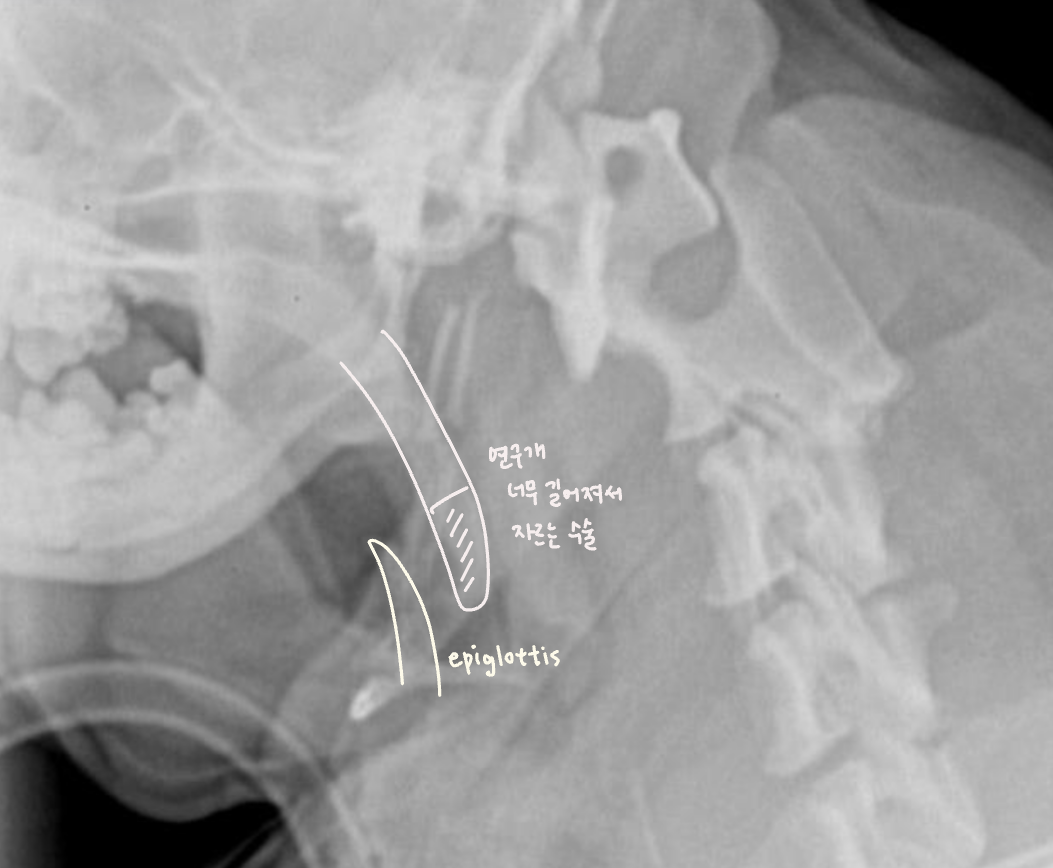

- English bulldog, Pug, Pekingese, French Bulldog, Bonston Terrier.. ์์ธ - Skull์ base๊ฐ ์ ์ ์ ์ผ๋ก ์งง์ - ๊ตฌ์กฐ์ ์ผ๋ก ์ผ๊ตด์ด ์งง์ ๊ตฌ์กฐ๊ฐ ๊ณผ๋ฐ๋จ Complex - stenotic nares (๋น๊ณตํ์ฐฉ) - soft palate edema & elongation (์ฐ๊ตฌ๊ฐ๋ ธ์ฅ) - laryngeal edema, saccules, collapase, paralysis - (dynamic) pharyngeal collapse GI complication - Hiatal hernia - gastroesophageal reflux (์ญ๋ฅ์ฑ ์๋์ผ) |

| Pharyngeal collapse : ํธ๊ธฐ ๋ ์ข์์ง - ์ฆ์์ ํก๊ธฐ์์ ๋ ์ฌํจ (ํก๊ธฐ์ฑ ํธํก๊ณค๋) ![]() ![]() |